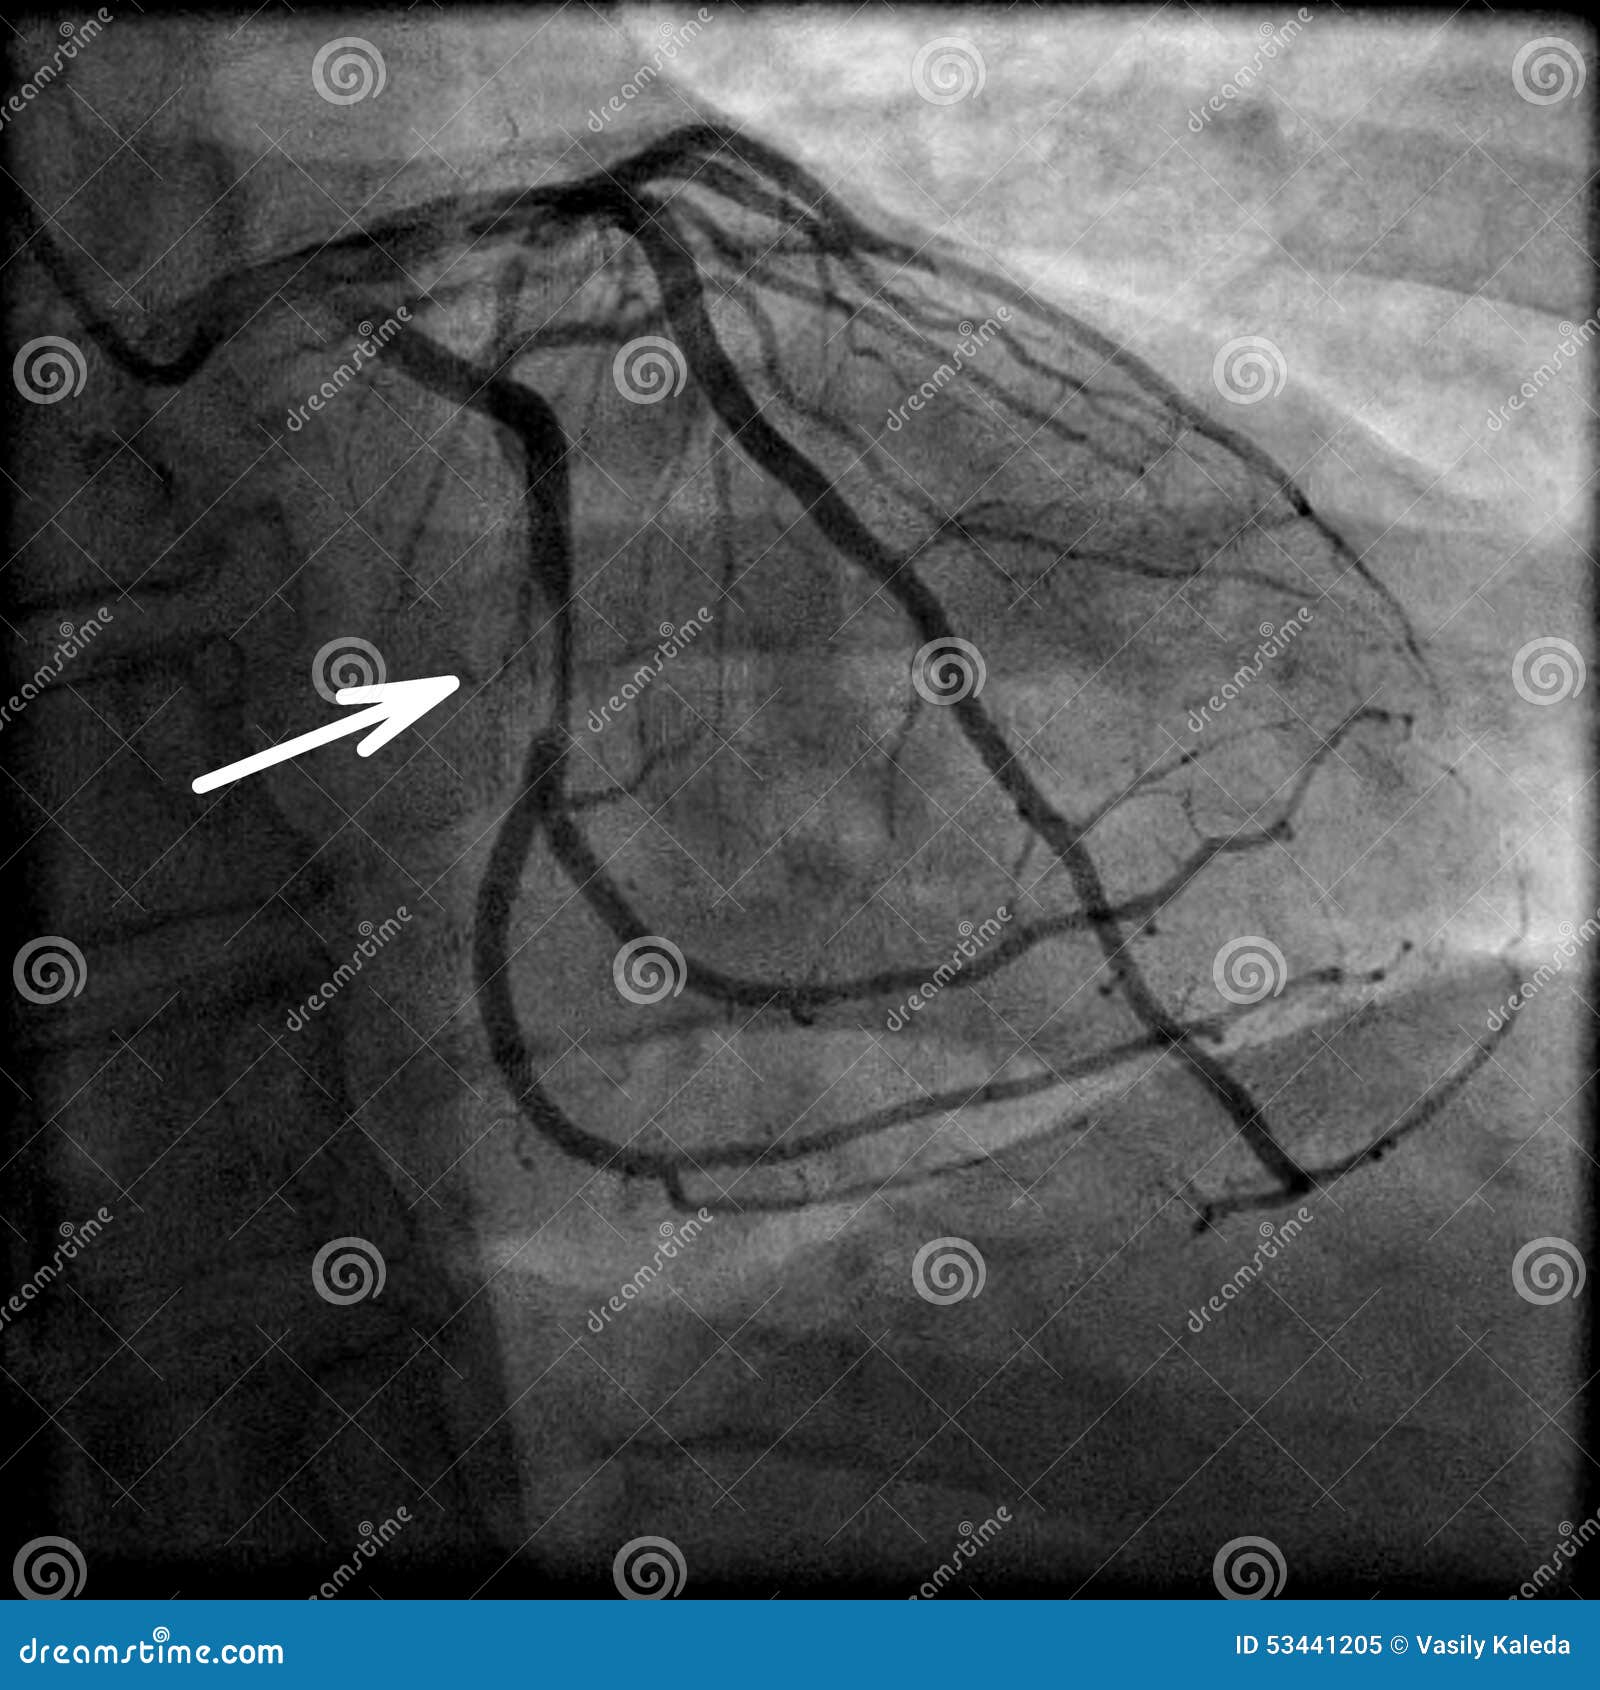

Хроническая окклюзия артерий: причины, симптомы и лечение